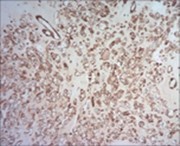

Parachordoma is immune reactive to cytokeratin CAM 5.2 and glial fibrillary acidic protein (50%). A subset of tumour cells are immune reactive to CD99 and smooth muscle actin (SMA). Stroma is intensely highlighted with an alcian blue stain wherein staining intensity is reduced following hyaluronidase digestion. Tumour cells are immune reactive to epithelial membrane antigen (EMA), CK8/18, S100 protein, calponin (50%), vimentin, type IV collagen and CD117 6.

Tumour cells are immune non reactive to CK1/10, cytokeratin AE1/AE3, CK20, CK7, CK19, CK12-17,smooth muscle actin (SMA), muscle specific actin (MSA), carcino-embryonic antigen (CEA), desmin, CD34, CD31, CD10, glial fibrillary acidic protein (GFAP), p63, TFE3, melan -A, brachyury, Human Melanoma Black-45 (HMB-45), D2-40 and α- inhibin.

Type IV collagen is immune reactive, envelops clusters of tumour cells and articulates a nest- like appearance 6, 7.

Figure 7.Parachordoma depicting immune reactivity to S100 protein 16.

Figure 8.Parachordoma demonstrating immune reactivity to vimentin 16.